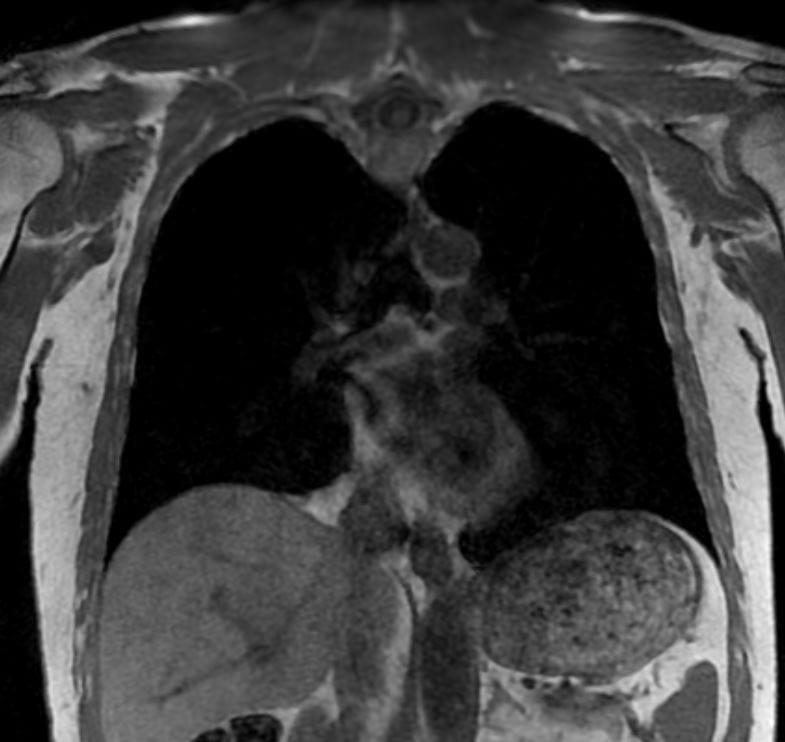

En MR-scanning af brystkassen (thorax) er en avanceret billeddiagnostisk undersøgelse, der giver detaljerede billeder af brystområdet uden brug af røntgenstråling. Vores 3 tesla MR-scanner skaber ekstremt præcise billeder ved hjælp af et kraftigt magnetfelt, der er ca. 60.000 gange stærkere end jordens magnetfelt.

Brystkassen (thorax) omfatter ribben, lunger med lungesæk (pleura), bronkier og de centrale dele (mediastinum), som indeholder hjertet, de store blodårer, luftrøret og spiserøret. En MR-scanning kan skabe detaljerede billeder af både hårde og bløde væv i dette område.

Eksempler på MR Scanninger